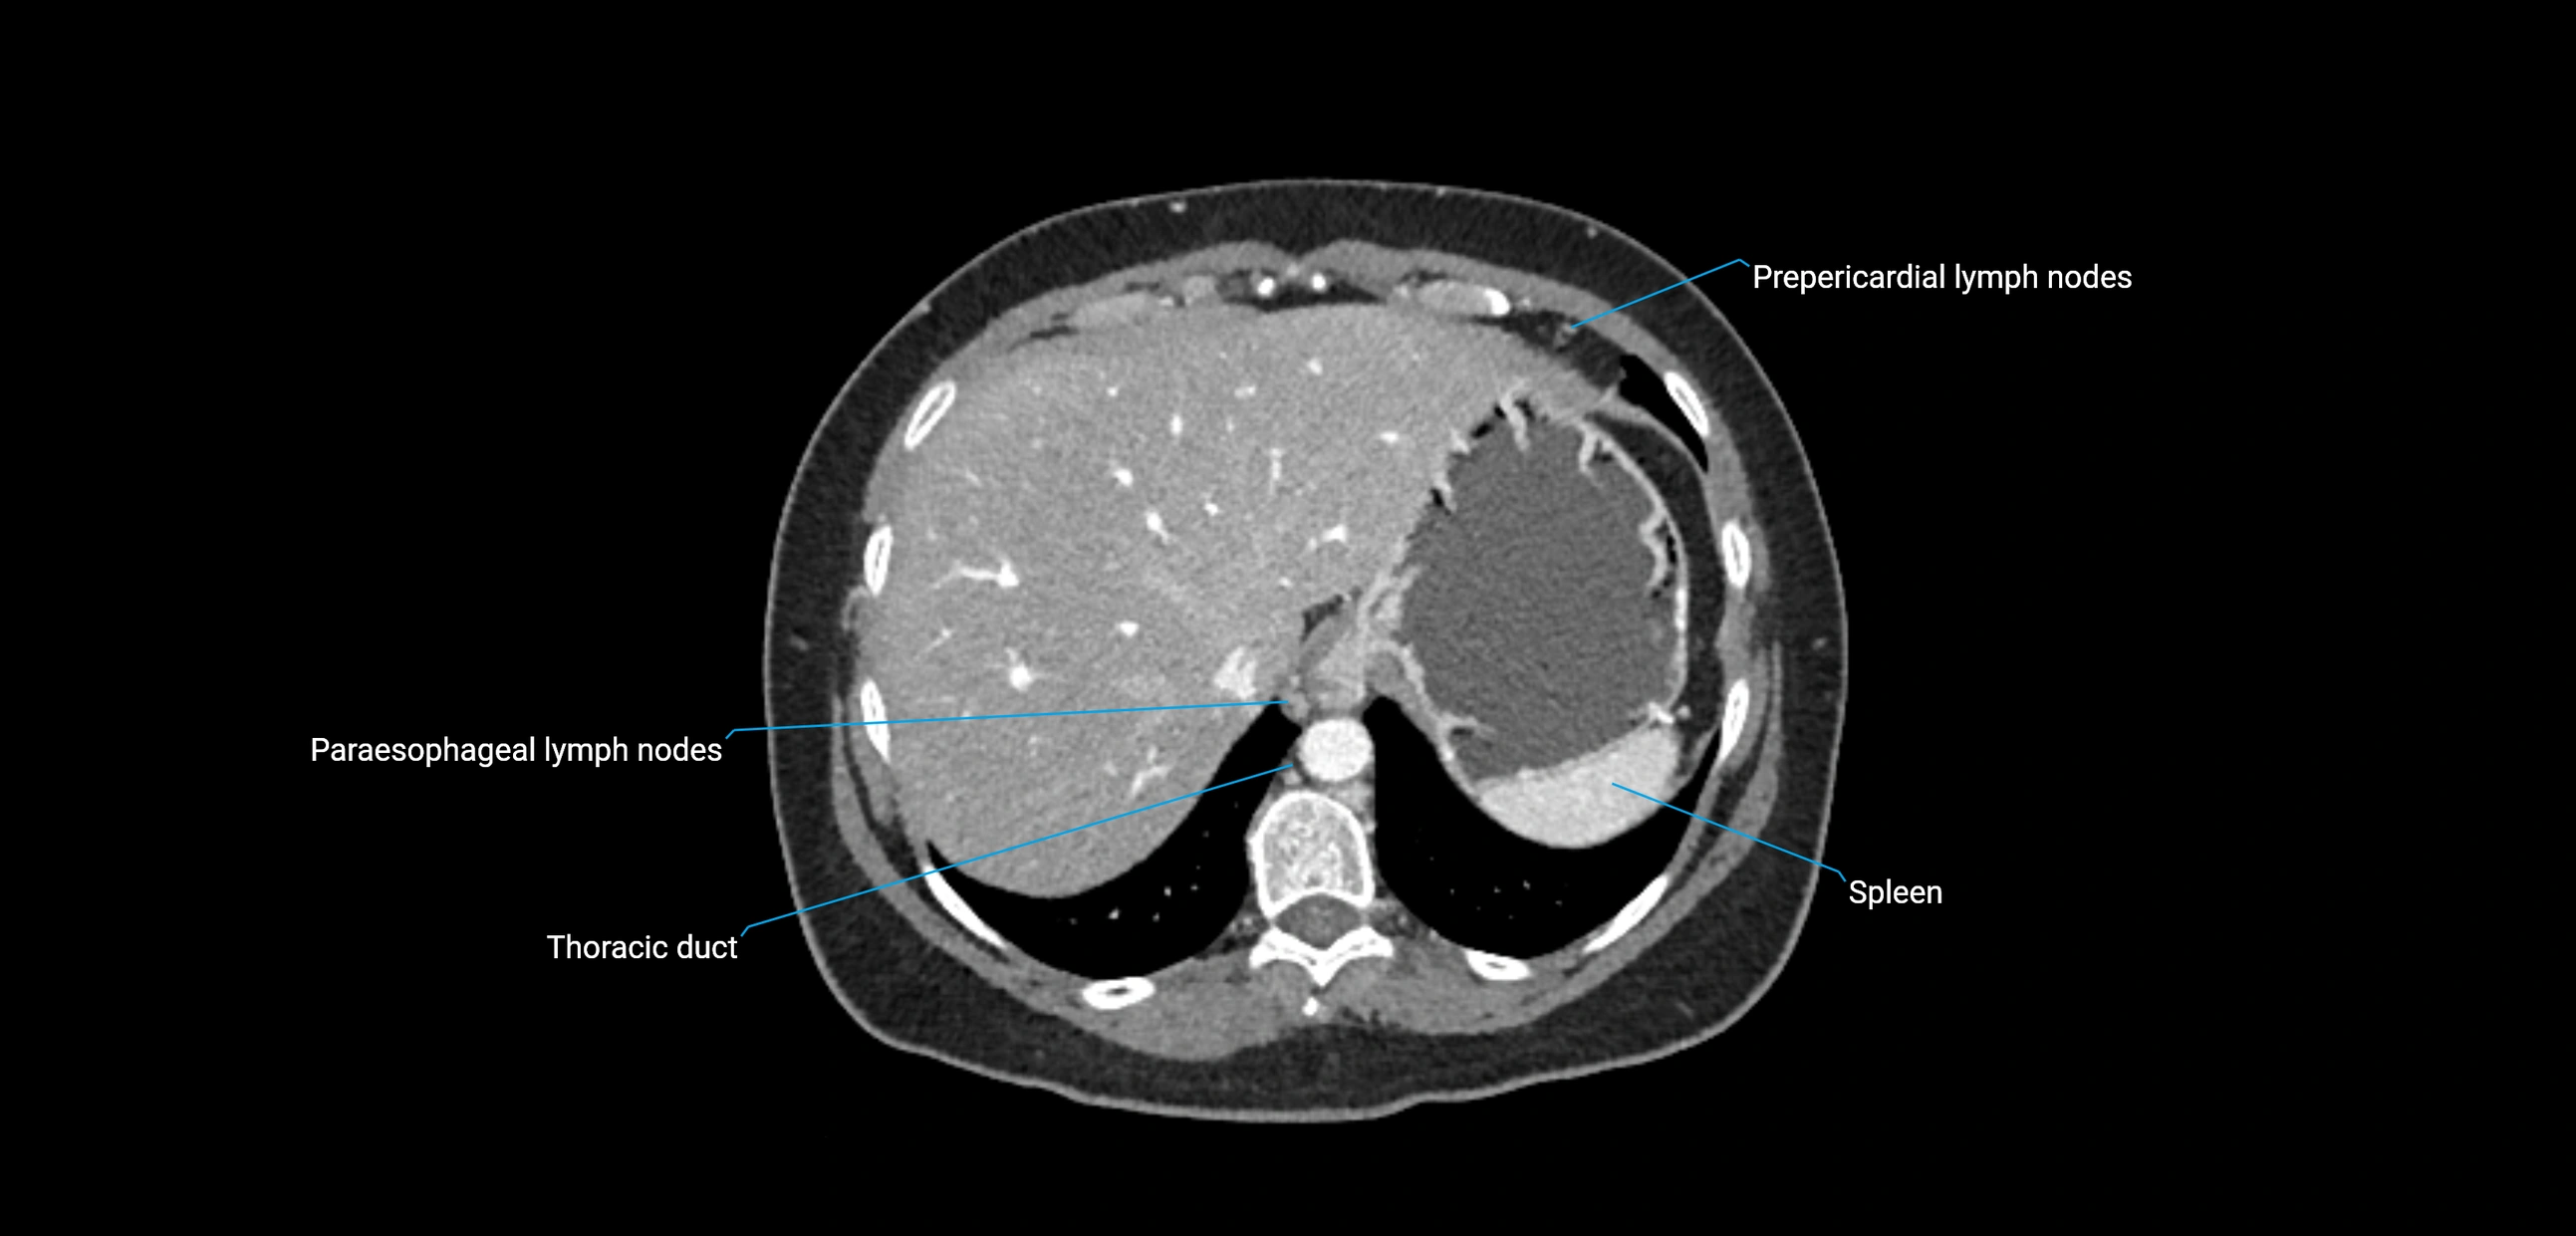

MRI images

image